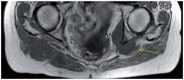

The purpose of this article is to familiarize the reader with the anatomy of the major pelvic nerves and the clinical features of associated lumbosacral plexopathies. To demonstrate this we illustrate several cases of malignant lumbosacral plexopathy on computed tomography, magnetic resonance imaging, and positron emission tomography/computed tomography. A new lumbosacral plexopathy in a patient with a prior history of abdominal or pelvic malignancy is usually of malignant etiology. Biopsies may be required to definitively differentiate tumour from posttreatment fibrosis, and in cases of inconclusive sampling or where biopsies are not possible, follow-up imaging may be necessary. In view of the complexity of clinical findings often confounded by a history of prior surgery and/or radiotherapy, a multidisciplinary approach between oncologists, neurologists, and radiologists is often required for what can be a diagnostic challenge.